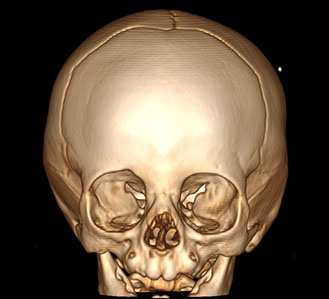

"Plagiocephaly"si olan bir küçük bebeğe ait 3D kranial BT rekonstrüksiyonu. Burada kafanın bir tarafındaki ön suturun erken kapandığı ve yüz şeklini de değiştirdiği izleniyor.